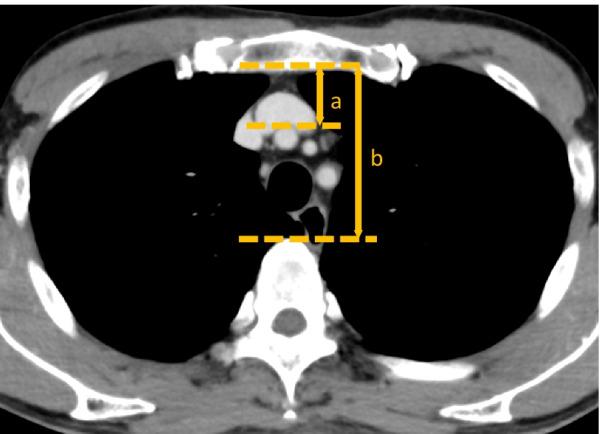

This study included 66 patients who underwent esophagectomy with retrosternal reconstruction using a gastric tube. All patients routinely underwent contrast-enhanced computed tomography (CT) on the 4th postoperative day. Low-molecular-weight-heparin (LMWH) was routinely administered by the 2nd postoperative day. To evaluate retrosternal space's width, (a) The distance from sternum to brachiocephalic artery and (b) the distance from sternum to vertebra were measured by preoperative CT, and the ratio of (a) to (b) was defined as the width of retrosternal space.

本研究纳入了 66 例行胸骨后胃管重建的食管癌切除术患者。所有患者术后第 4 天常规行增强 CT 检查。术后第 2 天常规给予低分子肝素(LMWH)。为评估胸骨后空间的宽度,(a)术前 CT 测量胸骨至头臂动脉的距离,(b)胸骨至椎体的距离,并定义(a)与(b)的比值为胸骨后空间的宽度。